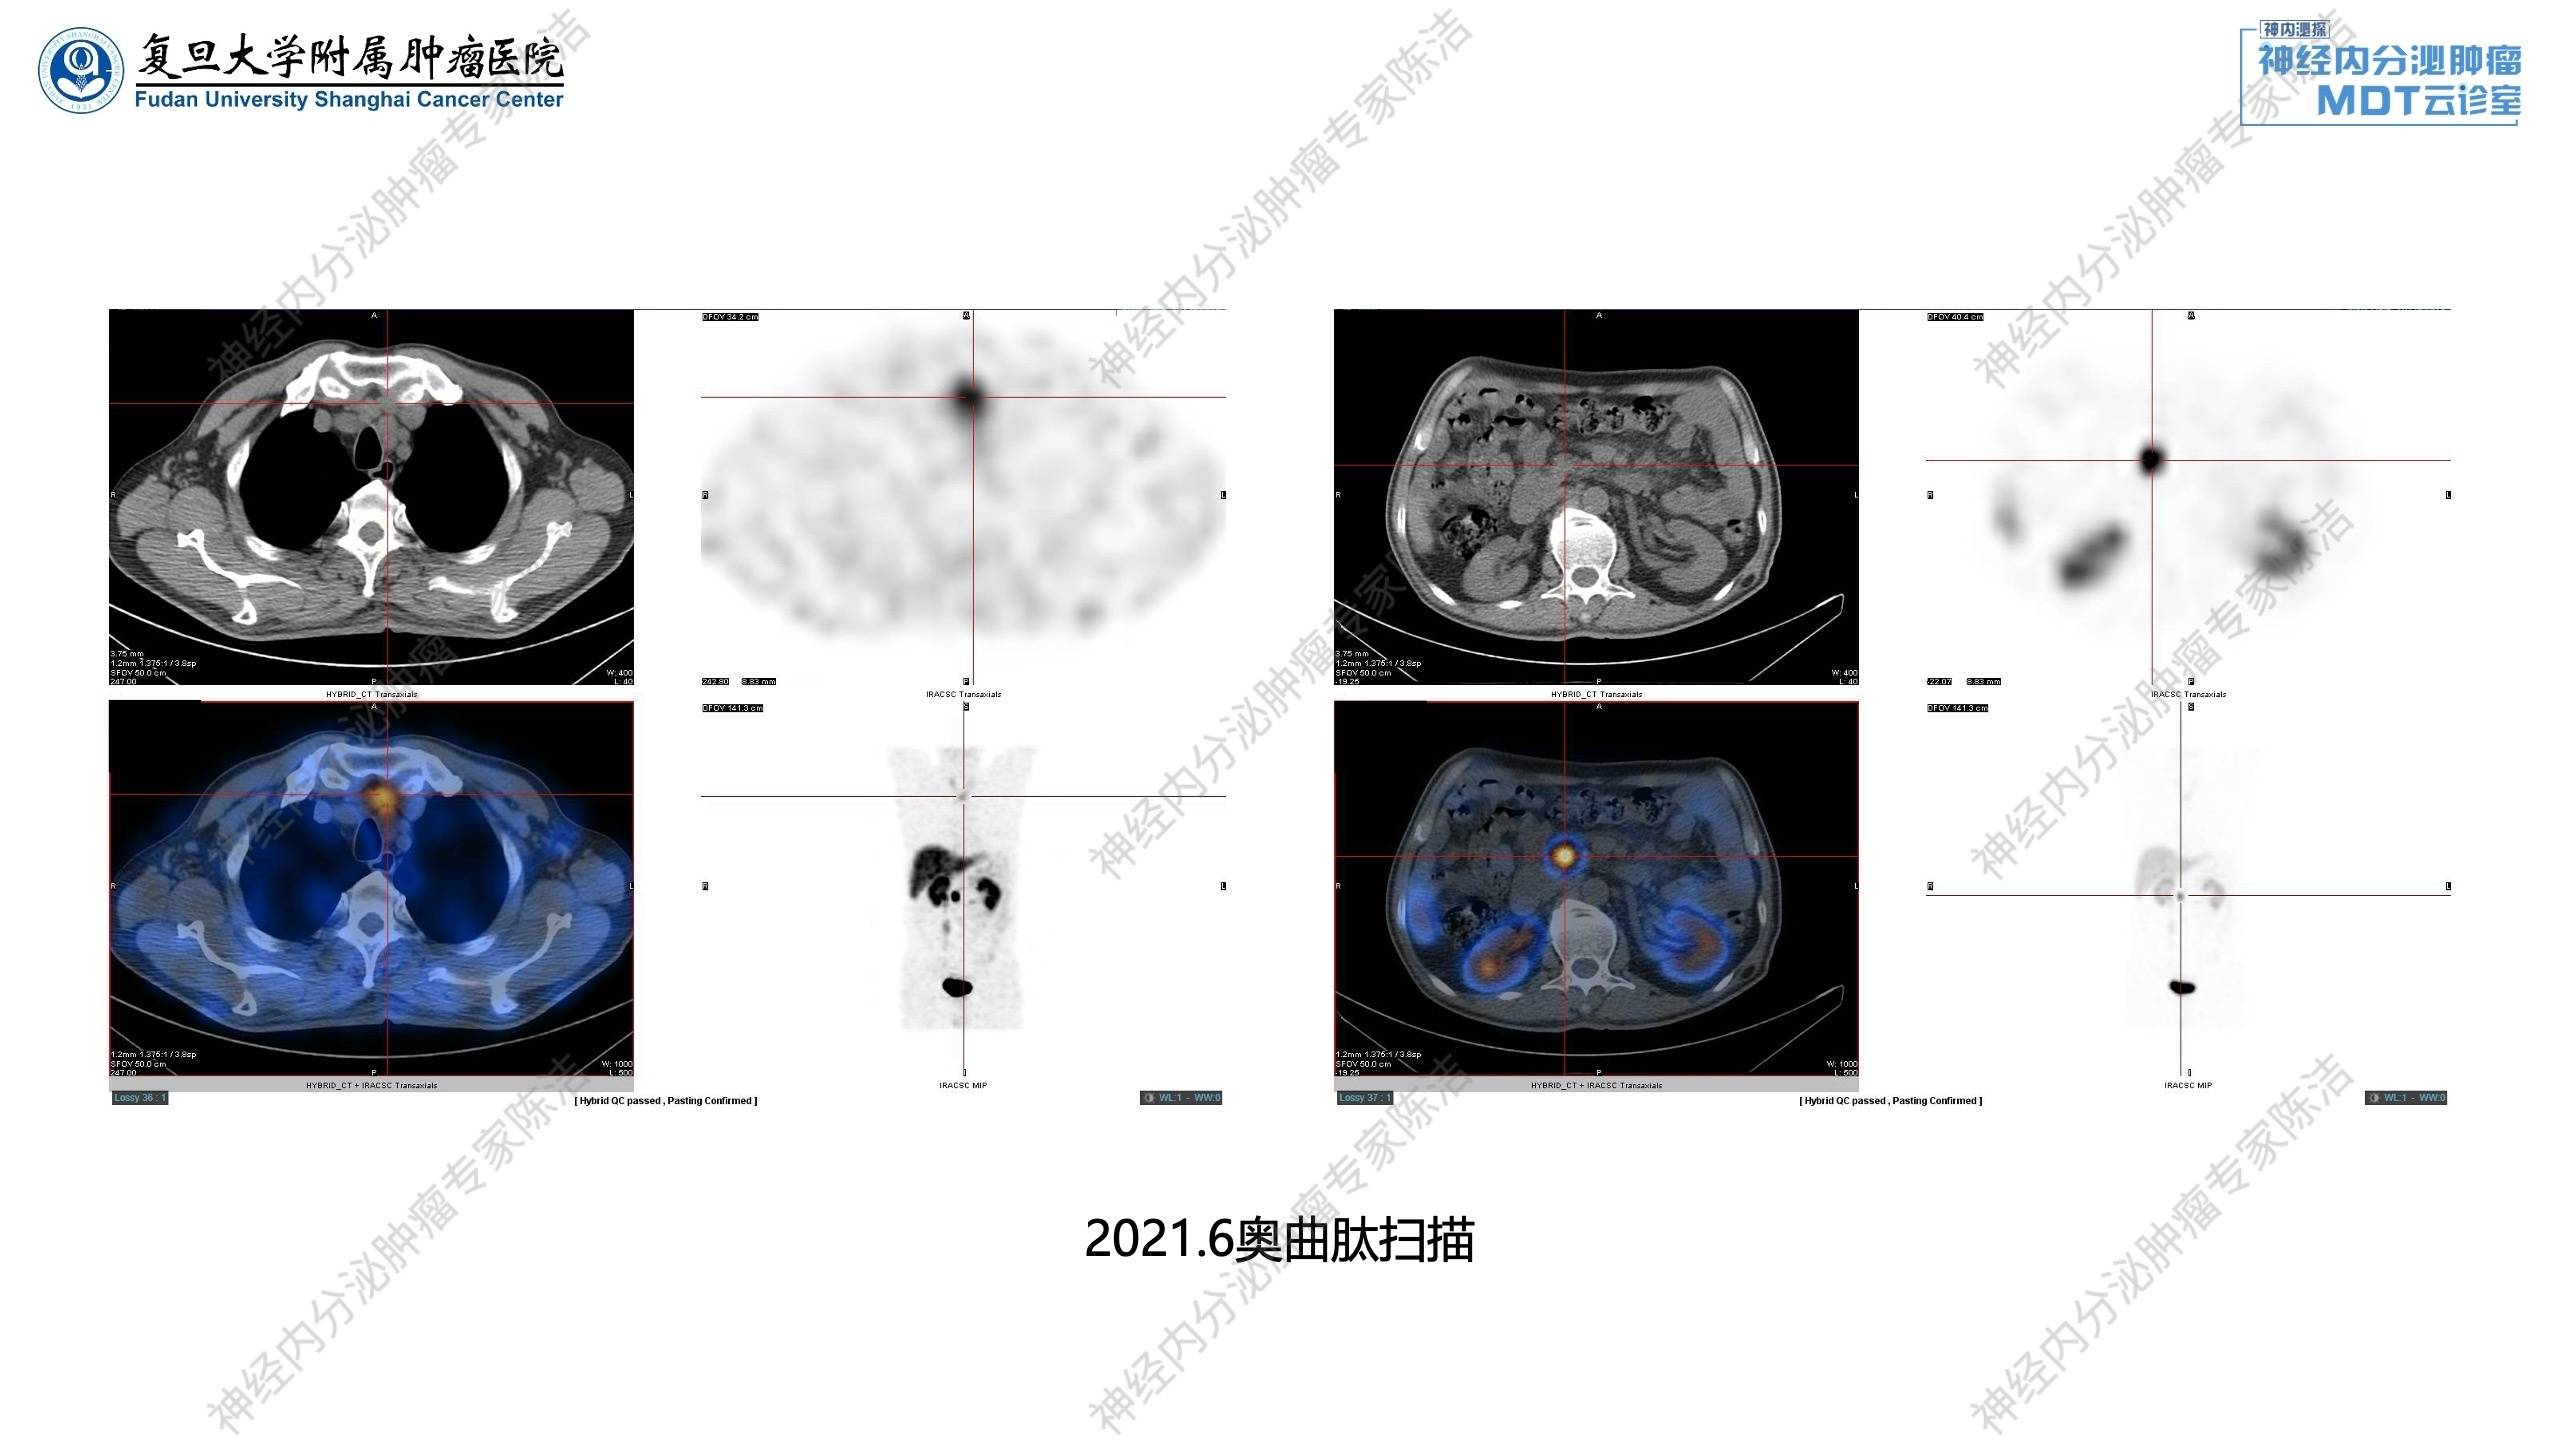

2021年6月:奥曲肽扫描显示:胰尾神经内分泌肿瘤术后残端及胰腺钩突、左侧锁骨上、高位气管旁、肝胃间隙、腹膜后、胰腺周围淋巴结生长抑素受体高表达,甲状腺右叶结节伴生长抑素受体高表达。

核医学科徐俊彦教授:该患者最初进行的是99mTc-TOC扫描,虽然分辨率有限,但仍显示了胰腺残端及纵隔淋巴结的SSTR高表达。随后进行的68Ga-DOTANOC-PET/CT提供了更清晰的图像,不仅确认了SSTR的高表达,还发现了更多微小病灶。